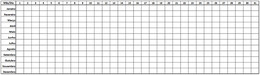

TemperaturaDiaria.jpg |